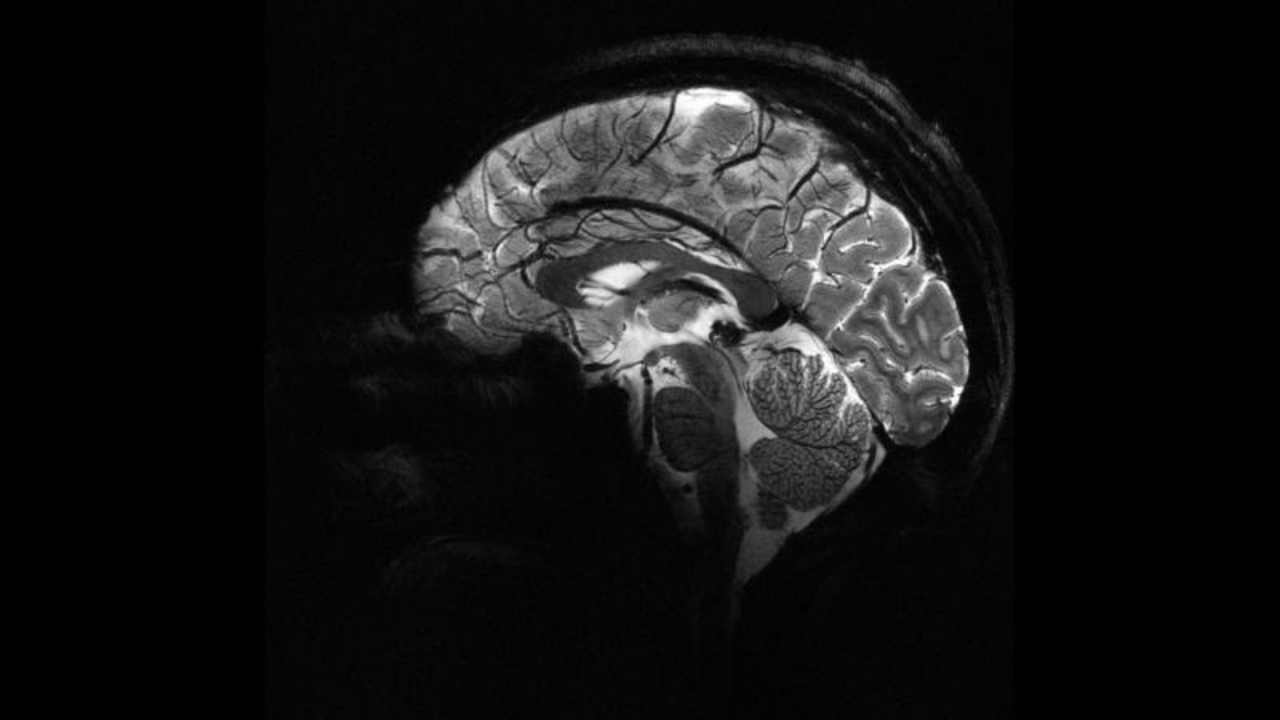

Epilepsiye farklı nedenler yol açsa da, vakaların yaklaşık yüzde 30’u beyindeki yapısal anormalliklerden kaynaklanıyor. Ancak bu lezyonlar, özellikle de beynin kıvrımlarının derinliklerinde saklı olan en küçük olanlar, çoğu zaman MR görüntülerinde fark edilmiyor.

ScienceAlert'daki habere göre Melbourne Kraliyet Çocuk Hastanesi’nden pediatrik nörolog Emma Macdonald-Laurs liderliğindeki ekip, çocuk beyin görüntüleri üzerinde yapay zekâ modeli eğiterek yaban mersini büyüklüğünde ya da daha küçük lezyonları ortaya çıkarmayı başardı.

Araştırmada kortikal displazi ve fokal epilepsi hastaları üzerinde testler yapıldı. Daha önce MR sonuçları “normal” raporlanan bu çocukların yüzde 80’inde aslında gizli lezyonlar olduğu belirlendi.

Yapay zekâ aracı hem MR hem de PET taramalarını analiz ettiğinde, bir test grubunda yüzde 94, diğerinde yüzde 91 başarı oranı yakaladı. İlk gruptaki 17 çocuktan 12’si beyin lezyonlarının çıkarılması için ameliyat edildi ve 11’i artık nöbetsiz yaşıyor.